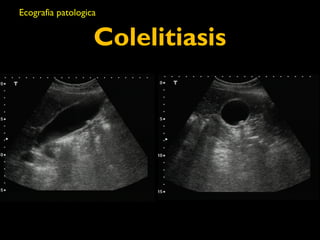

Colelitiasis

• Caracteristicas ecograficas

• Estructuras ecogénicas dentro de la luz

vesicular libre de ecos

• Sombra acustica con margenes “limpios”

• Dependencia gravitacional

• Son usualmente moviles

• Patrones de imagenes

• Foco ecogénico, sombra acustica limpia,

dependencia gravitacional

• Gravedad

• Lito grande

• Signo de eco de la pared